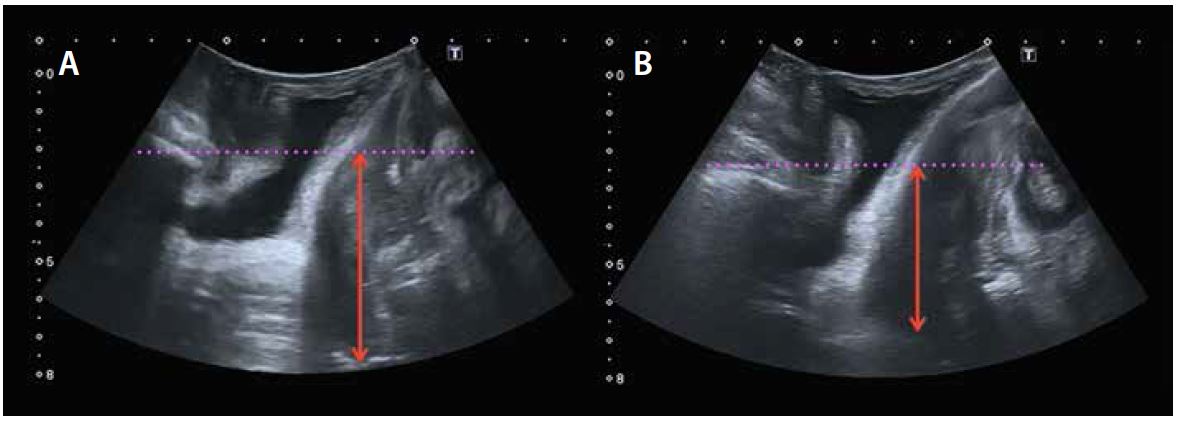

Під час ультразвукової оцінки середнього відділу дуже важливо оцінити рухливість матки, щоб визначити різницю між опущенням матки та подовженням шийки матки без опущення матки. Параметром, який найкраще дозволяє діагностувати опущення матки, є різниця між станом спокою та маневром Вальсальви між лобково-матковим дном (червона лінія на мал. 7) понад 15 мм.

Малюнок 7. Діагностика опущення матки з різницею між положенням спокою (A) і положенням Вальсальви (B), відстань між лобком і матковим дном > 15 мм.